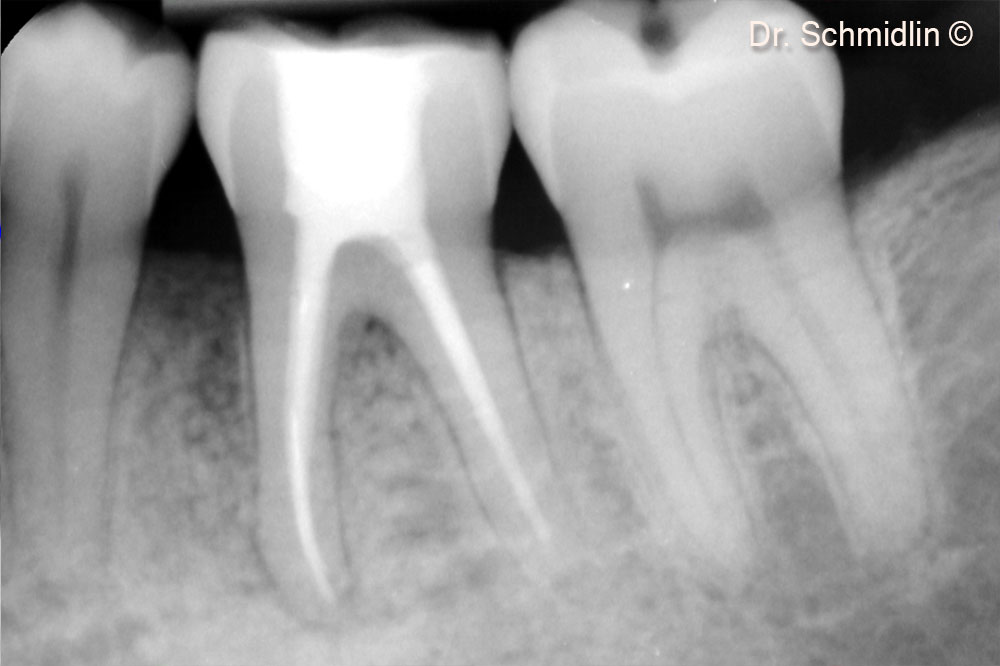

Pre-op X-Ray

Post-op X-Ray